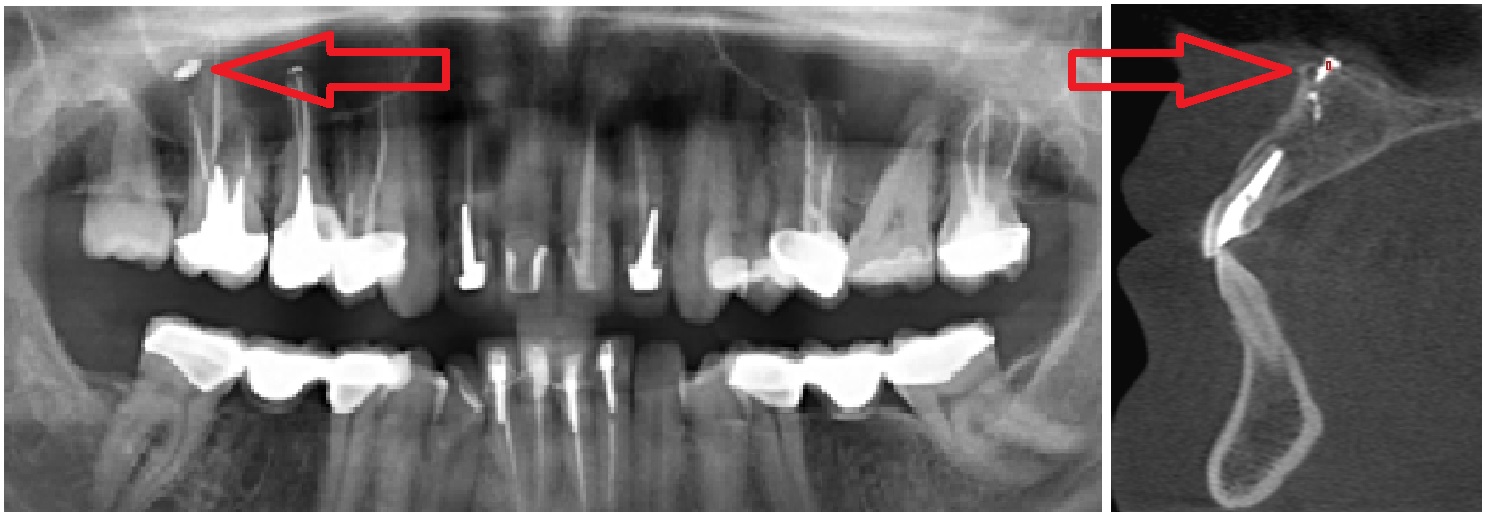

Вариант 1. Давление пломбировочным материалом на ветви тройничного нерва, луночковые нервные сплетения. После удаления нерва и пломбировки каналов болит зуб.

Стрелками показаны фрагменты пломбировочного материала (вид спереди и сбоку), который при пломбировании канала выпал за пределы зуба и «упёрся» в область залегания ветви тройничного нерва. У пациента долго болел зуб после лечения пульпита, затем онемела верхняя губа и часть щеки.